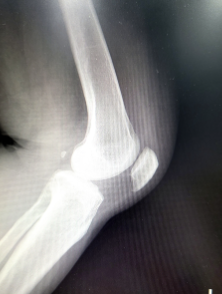

슬개골은 대퇴골과 종아리뼈 사이에 위치하며 대퇴골과 함께 무릎 관절을 형성하는 삼각형 모양의 큰 뼈입니다. 슬개골은 대퇴골에 부착된 근육과 인대에 의해 제자리에 고정되며 무릎 관절의 움직임에 중요한 역할을 합니다. 슬개골에 이상이 생기면 무릎 통증, 부종, 무릎 갈라짐 등의 증상이 나타날 수 있다.

슬개골 연골 연화증은 슬개골과 대퇴골 사이에 위치한 슬개골 연골이 퇴화, 손상 또는 연화되는 상태입니다. 주로 중년 이상의 여성에게 발생하며 골다공증, 슬개골의 비정상적인 움직임, 유전적 요인에 의해 발생합니다. 증상으로는 슬개골 통증, 불안정성 및 퇴행성 변화가 있습니다. 진단은 X-ray, MRI, 초음파 등으로 확인할 수 있으며 치료는 보존적 치료(약물치료, 근육강화운동 등)와 수술적 치료(슬개골 전진술, 전후방 창상수술 등)가 있다. 빠른 진단과 치료가 필요하며 방치할 경우 슬개골 퇴행성관절염, 연골파괴 등 심각한 합병증이 발생할 수 있다.